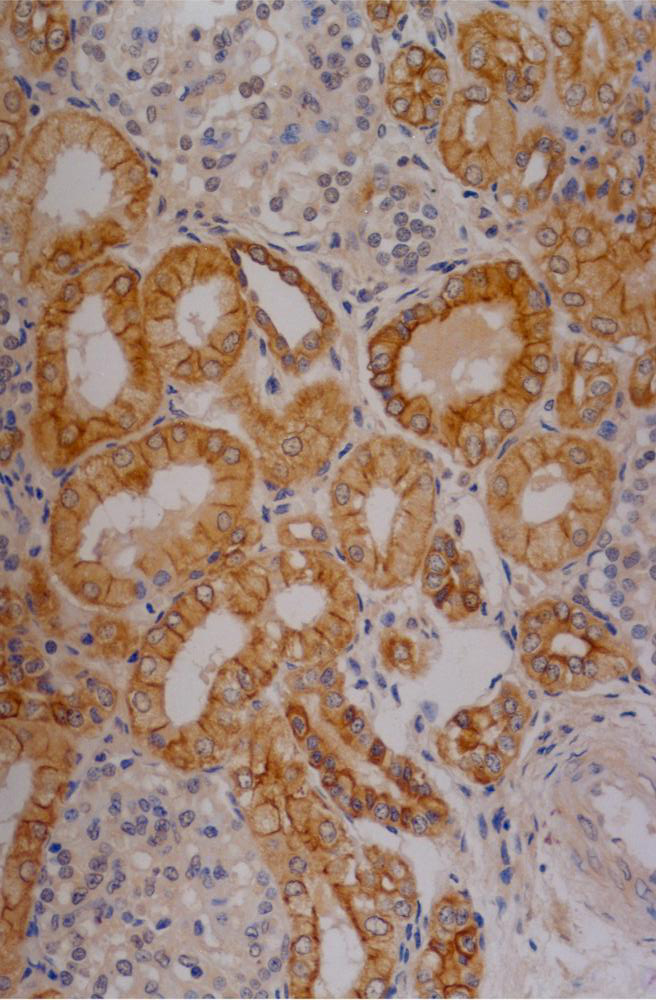

Immunohistochemistry staining of human kidney (paraffin-embedded sections) with anti-Cytokeratin 18 (C-04).